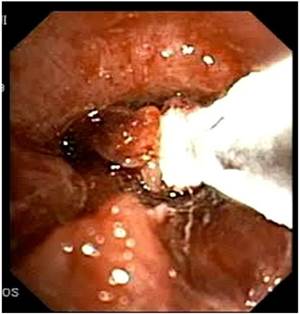

Figure 3

Argon Plasma Coagulation.

J Cancer Image

Recent ACCP Lung Cancer Guidelines mention several interventional bronchoscopic modalities for palliation of dyspnea due to inoperable malignant CAO.[28] The results of the present prospective, controlled study confirm the considerable benefit of interventional bronchoscopic management of such patients and make an argument that patients with malignant CAO treated endoscopically have less dyspnea, better QoL, improved physical function and longer survival than patients with oncologic treatment alone. Combined interventional and oncologic treatment should be considered in any multidisciplinary cancer care program and offered to all patients with lung cancer and inoperable CAO, especially when post-obstructive atelectasis is present. Since such an approach is often limited by the lack of interventional equipment and skills, the urgent need for respiratory physicians' training in therapeutic bronchoscopy and development of interventional units is also highlighted.[29] (Figures 3-8) Additional treatment with radiotherapy could be used based on the patient performance status and local interventional prior or after stent placement-debulking.[30-36] Multimodality treatment is necessary for patients with central tumors local treatment should be accompanied with systematic treatment when possible.